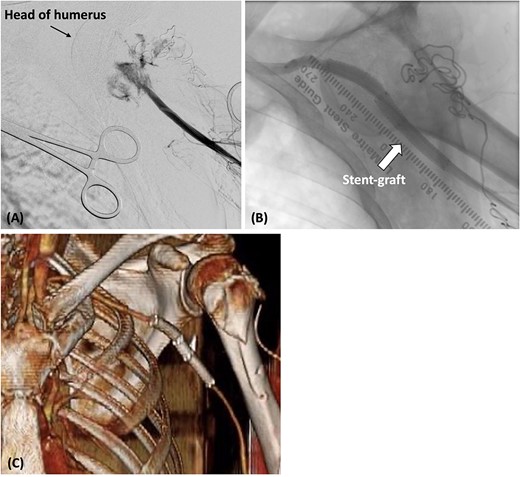

(A) The catheter was inserted from the left brachial artery, and angiography revealed the extravasation of the axillary artery. (B) Stent grafts were placed at the site of the axillary artery rupture to confirm that there was no leakage. (C) Postoperative contrast-enhanced CT revealed that blood flow in the axillary artery was maintained.

Postoperatively, cefazolin was administered intravenously for 1 week after endovascular repair. The radial artery was palpable, and contrast-enhanced CT confirmed that the absence of any leakage from the axillary artery (Fig. 2C). The patient experienced a smooth recovery, except for the presence of brachial plexus palsy. He was discharged on the 10th day, and no infection of the wound or stent grafts was observed during the 5-month outpatient follow-up.